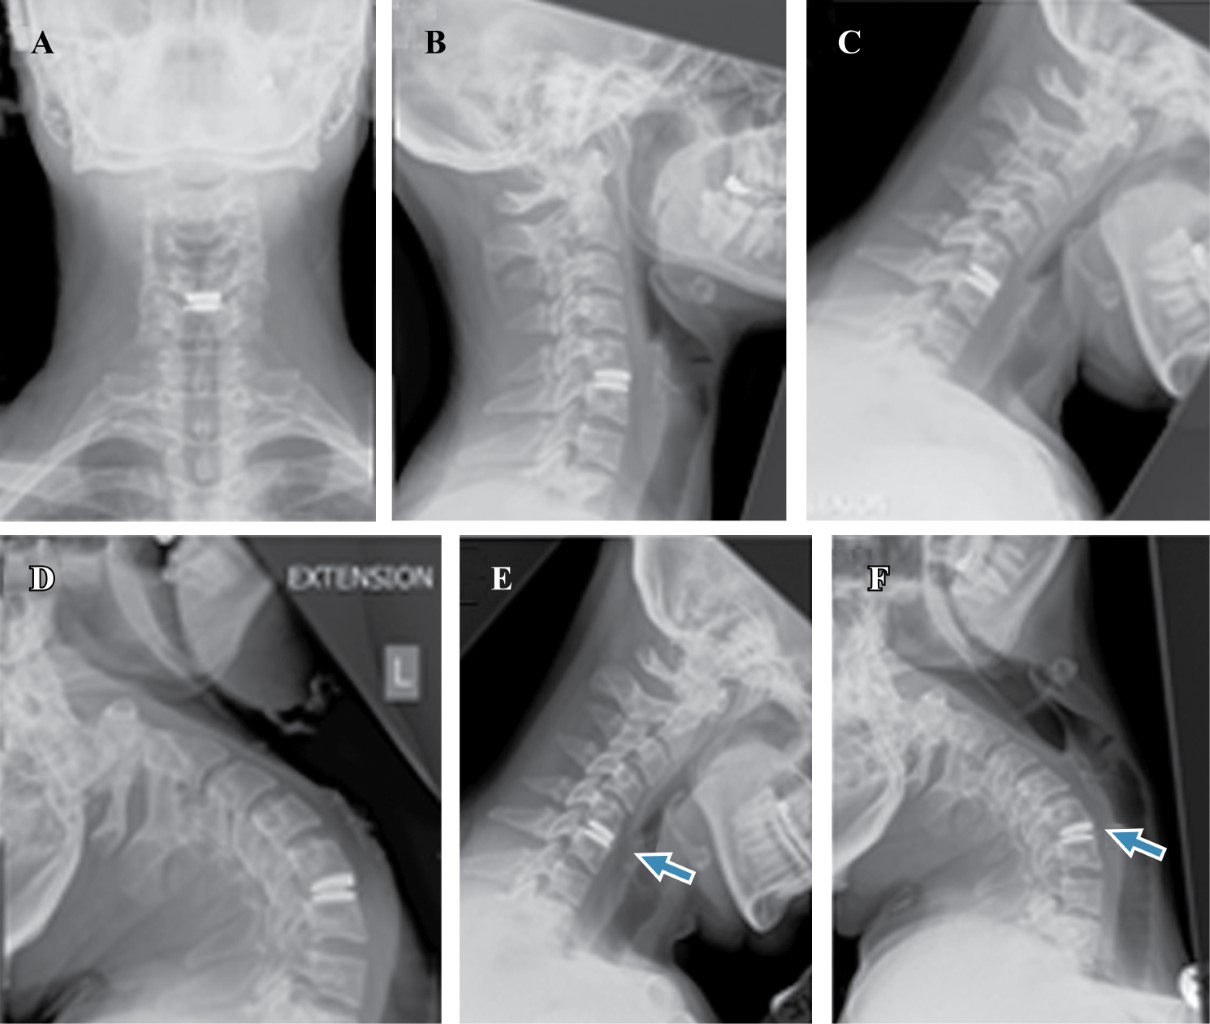

Three weeks after procedure, with a healed wound and a stable TDR (Figure 3A-D) she was allowed to return to training along with a rehabilitation program. Three months after surgery the patient competed in the world champion winning a medal, losing only the title fight and at that time and more importantly, having no symptoms during and after that event.

The patient has completed seven years follow up, did not stop training, and has become a coach, a natural path of progression for a fighter. Up to this last follow-up visit patient is symptoms free from arm, neck pain and has intact neurological exam. At the level C5-6 there was anterior calcification, but still allowing movement and without clinical relevance. The dynamic radiographs showed a ROM of 13º (Figure 3E and F) and in physical exam there was full ROM in her neck. Although C4-5 had slightly increased motion in flexion, the adjacent levels displayed preserved intervertebral disc height. No complications or adverse events related to the TDR were observed.